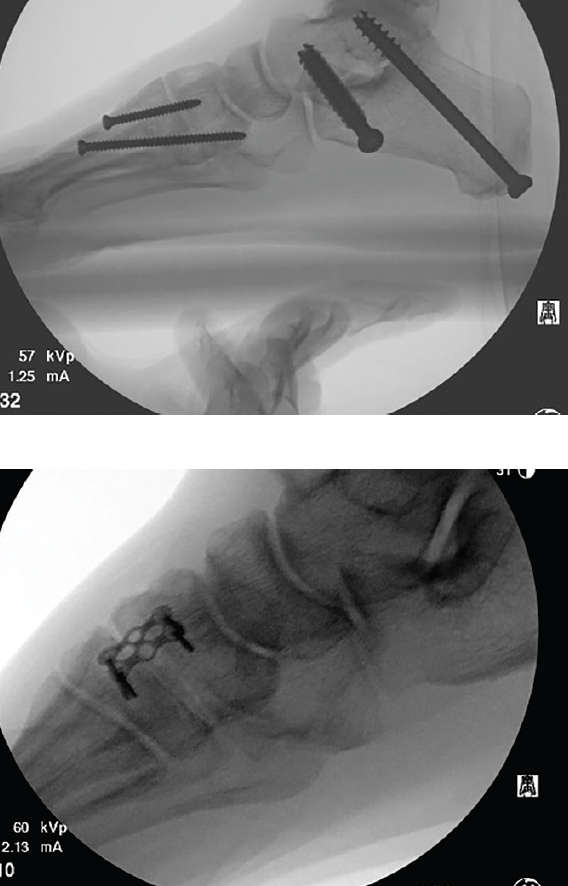

Boffeli and Waverly described a simulated weight-bearing long-leg axial (WB LLA) image, primarily used to evaluate the frontal plane alignment of the calcaneus in relation to the long axis of the tibia.5 The simulated WB LLA imaging protocol often applies to rearfoot osteotomy or arthrodesis, calcaneal osteotomy or fracture repair, rearfoot arthrodesis, ankle arthrodesis, total ankle arthroplasty, and supra-malleolar osteotomy. This image aims to superimpose the second metatarsal through the tibia while attempting to capture a simulated weight-bearing resting foot position. The ankle position is at 90 degrees, with the foot loaded in a simulated weight-bearing position using a radiolucent flat plate. One positions the C-arm at a 45-degree angle, with the leg rotated to position the second metatarsal at 90 degrees to the floor to achieve the desired tibia-through-second metatarsal alignment (see images below). There is no attempt made to alter the foot-to-leg position, which is held in simulated resting calcaneal stance position. The goal is to capture as much of the tibia as possible without cutting off the heel. Positioning the image intensifier close to the toes helps in this regard.5

weight-bearing intraoperative long leg axial imaging, which requires specific patient and imager positioning. In our practice, we attempt to image the

second metatarsal through the tibia for

reproducible and consistent results.